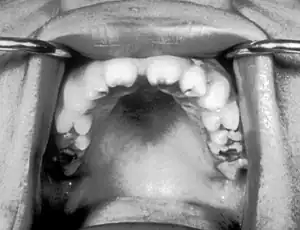

Notched incisors known as Hutchinson's teeth which are characteristic of congenital syphilis

• Blunted upper incisor teeth known as Hutchinson's teeth

A frequently-found group of symptoms is Hutchinson's triad, which consists of Hutchinson's teeth (notched incisors), keratitis and deafness and occurs in 63% of cases.[18]